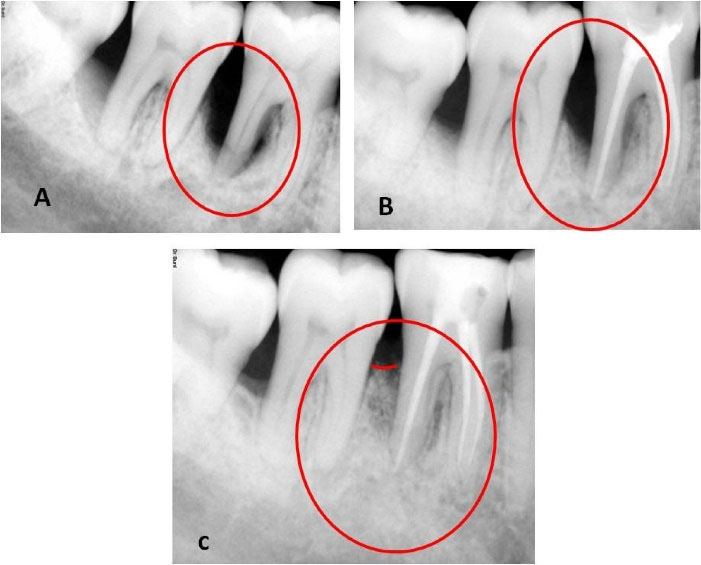

A healthy patient (male, age = 42 years) presented with a chief complaint of discomfort and food impaction in the lower right back teeth region and bad breath for five months. Intraoral examination revealed a full constituent dentition, generalized moderate accumulation of dental biofilm, calculus, and generalized bleeding on probing, more prominent in the lower right second premolar to the third molar region (#45 to #48). Food impaction was observed between the lower right first and second molars (#46 and #47). Mild tenderness on percussion (TOP) was elicited with #46 and #47. Grade I mobility and occlusal and buccal caries were detected with #46. The clinical attachment level (CAL) and probing pocket depth (PPD) were 8 mm in the interdental region of #47 and #48 and 4 mm between #45 and #46. However, the CAL was 9 mm, and PPD was 8 mm in the interdental region of #46 and #47 due to 1 mm of gingival recession on the distobuccal root of #46 (Table 1). A long-cone paralleling technique and intraoral direct digital periapical radiovisiograph (RVG-Suni Medical Imaging, Apteryx Inc., Acron, Ohio, USA) were used for radiographic evaluation (Table 2). The radiographs revealed angular bone loss in the lower right first and second molar (#46 and #47) region, with the base of the vertical defect extending to the apex of the distal root of the lower right first molar (#46); however, there was no sign of root damage (Figure 1). Vitality test exhibited a delayed response with #46 and a positive response with #47. The patient was devoid of complicating factors such as diabetes and smoking, which could have affected the healing and treatment outcome. Based on the presentations and common classification by Simon et al.,6 the lesion was classified as primary periodontal lesions with secondary endodontic involvement and grade 3 endo-periodontal lesion in periodontitis patients as per the 2017 World Workshop Classification.7

Figure 1.

Preoperative, postoperative, and follow-up radiographs. (A) Preoperative radiograph displaying endodontic-periodontal lesion. (B) Three-month follow-up displaying partial bone regain. (C) Nine-month follow-up displaying a significant bone regain

The patient was followed for one month after endodontic treatment with no evident changes in the clinical parameters; hence, we proceeded to surgical therapy. We also conducted post-surgical follow-up after a week, one month, 3 months, and 9 months. During the first follow-up appointment, the patient had no complaints of pain and discomfort and no tenderness on percussion. We reinforced oral prophylactic instructions. The sutures were removed ten days after surgery. During the one-month and three-month appointments, the patient displayed good oral hygiene. The surgical area displayed complete healing, no tenderness on percussion, and no tooth mobility. Radiographic evaluation three months after surgery displayed a partial bone fill (Figure 1). During the 9-month follow-up appointment, the periodontal lesion had significantly improved clinically and radiographically (Figures 1 and 3). A significant reduction in the periodontal probing depth and gain in the clinical attachment level was noted (Table 1). At any of these intervals, there was no attempt at subgingival instrumentation.